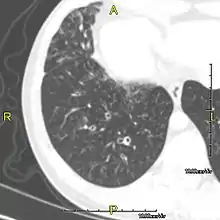

Around 80% of people with primary ciliary dyskinesia experience respiratory problems beginning within a day of birth. Many have a collapsed lobe of the lung and blood oxygen low enough to require treatment with supplemental oxygen.[1] Within the first few months of life, most develop a chronic mucus-producing cough and runny nose.[1] The main consequence of impaired ciliary function is reduced or absent mucus clearance from the lungs, and susceptibility to chronic recurrent respiratory infections, including sinusitis, bronchitis, pneumonia, and otitis media. Progressive damage to the respiratory system is common, including progressive bronchiectasis beginning in early childhood, and sinus disease (sometimes becoming severe in adults). However, diagnosis is often missed early in life despite the characteristic signs and symptoms.[2] In males, immotility of sperm can lead to infertility, although conception remains possible through the use of in vitro fertilization, there also are reported cases where sperm were able to move.[8] Trials have also shown that there is a marked reduction in fertility in females with Kartagener's syndrome due to dysfunction of the oviductal cilia.[9]

Many affected individuals experience hearing loss and show symptoms of otitis media which demonstrates variable responsiveness to the insertion of myringotomy tubes or grommets. Some patients have a poor sense of smell, which is believed to accompany high mucus production in the sinuses (although others report normal – or even acute – sensitivity to smell and taste). Clinical progression of the disease is variable, with lung transplantation required in severe cases. Susceptibility to infections can be drastically reduced by an early diagnosis. Treatment with various chest physiotherapy techniques has been observed to reduce the incidence of lung infection and to slow the progression of bronchiectasis dramatically. Aggressive treatment of sinus disease beginning at an early age is believed to slow long-term sinus damage (although this has not yet been adequately documented). Aggressive measures to enhance clearance of mucus, prevent respiratory infections, and treat bacterial superinfections have been observed to slow lung-disease progression. The predicted incidence is 1 in approximately 7500.[10]

When accompanied by the combination of situs inversus (reversal of the internal organs), chronic sinusitis, and bronchiectasis, it is known as Kartagener syndrome[3] (only 50% of primary ciliary dyskinesia cases include situs inversus).[11]